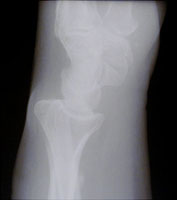

- Click on the image for a larger versionAPA radiograph of the wrist. There is irregularity of the distal radial margin. In addition, a fracture of the distal radius is appreciated.